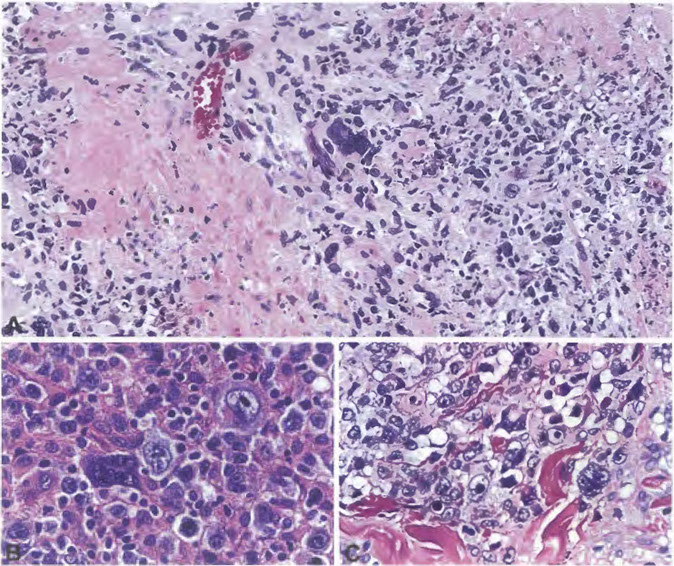

Post-Transplant Lymphoproliferative disorders (PTLD)

- Non-destructive PTLD

- Polymorphic PTLD

- Monomorphic PTLD (B- and T/NK-cell types)

-

- Monomorphic B-cell PTLD

- Monomorphic T/NK-cell PTLD

- Classic Hodgkin lymphoma PTLD